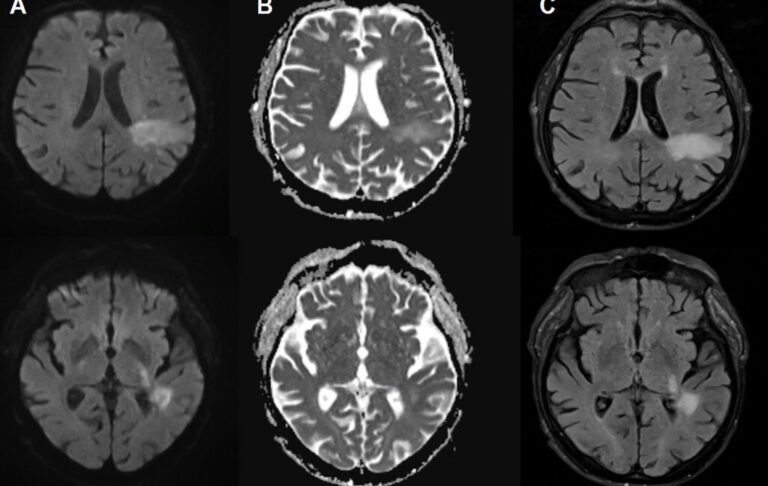

There’s a virus you may have never heard of before that is estimated to infect up to 90 percent of people and lurks silently in your cells throughout your life, but if activated, it will destroy your brain. If that’s…